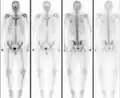

Osteopoikilosis Normal bone scan in a person with osteopoikilosis

Normal bone scan in a person with osteopoikilosis